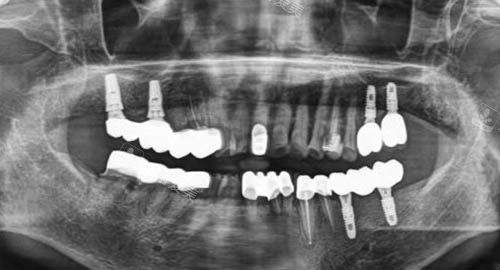

多颗牙齿种植ct

一方面,他们引进了国内外比较靠前的种植系统,这些种植体具有良好的生物相容性和稳定性,能够与牙槽骨紧密结合,大大提高了种植牙的成功几率。

另一方面,乐美口腔的医师团队在种植牙领域有着深厚的造诣,他们会在术前为患者进行齐全的口腔检查和评估,制定科学合理的种植方案。

在种植过程中,凭借优质的技术和丰富的经验,确保种植手术的更准一些性和靠谱性。

术后,还会对患者进行长期的跟踪和维护,让患者能够放心地使用种植牙。